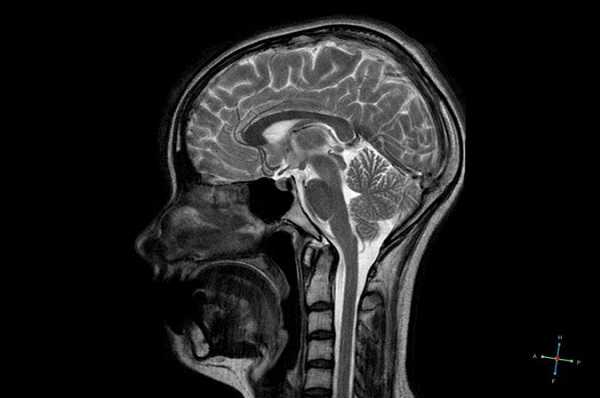

Снимок МРТ головного мозга в двух проекциях

Гипофиз - небольшая железа, расположенная в ямке турецкого седла клиновидной кости. Ее размеры в норме не превышают 2 см. От полости черепа гипофиз ограничен диафрагмой седла, а участок задней доли железы соединяется с гипоталамусом.

Наружная оболочка анатомического образования представляет собой соединительнотканную капсулу, покрывающую переднюю и заднюю доли гипофиза. Основная часть - аденогипофиз - составляет 80% от веса железы. Задняя доля - нейрогипофиз - представлена воронкой и нервной частью.

Анатомия гипофиза

Гипофиз - придаток головного мозга весом менее половины грамма, расположенный в особом углублении - ямке турецкого седла клиновидной кости черепа. Состоит из трех долей - передней (аденогипофиза), промежуточной и задней (нейрогипофиза). Гормоны, вырабатываемые питуитарной железой, влияют на рост человека, обмен веществ, гомеостаз, репродуктивную функцию и пр. Сделать МРТ содержимого турецкого седла обосновано при появлении жалоб, свидетельствующих о поражении нижнего мозгового придатка, изменениях в гормональном профиле. При новообразованиях небольшого размера для более четкой визуализации исследование всегда проводят с контрастированием.